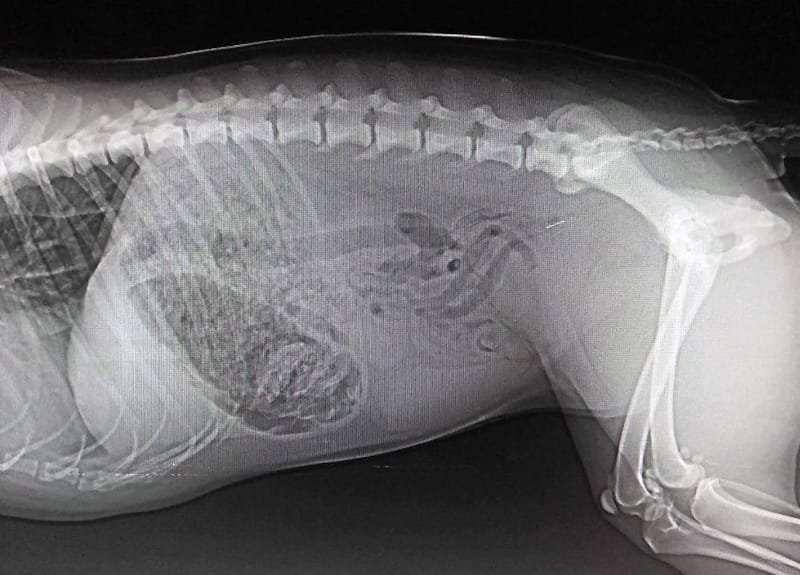

צילומי רנטגן